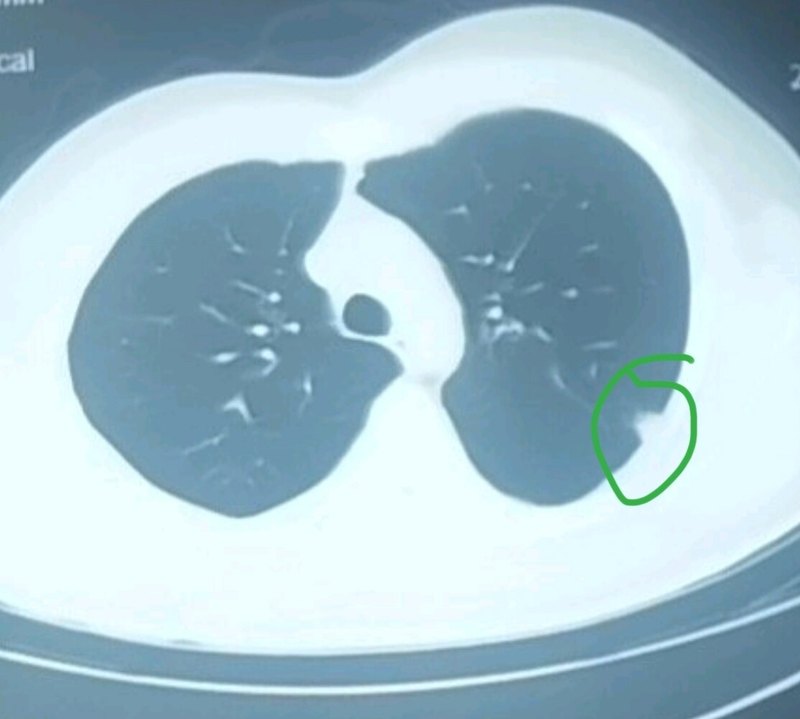

治療前該患者于外院行上肢肉瘤切除后,發(fā)現(xiàn)肺轉(zhuǎn)移。當(dāng)?shù)亟ㄗh化療。202207月我院CT示肺轉(zhuǎn)移,右圖為病理診斷腺泡狀軟組織肉瘤治療中經(jīng)病理復(fù)核后,采用靶向治療和免疫治療,療效好,副作用小。經(jīng)2年余治療后,無明顯不適。202412月CT示肺轉(zhuǎn)移得到長期控制,發(fā)生纖維化。治療后治療后2年治療2年半后petct顯示腫瘤無活性,該治療能保證患者生活質(zhì)量,同時(shí)療效好